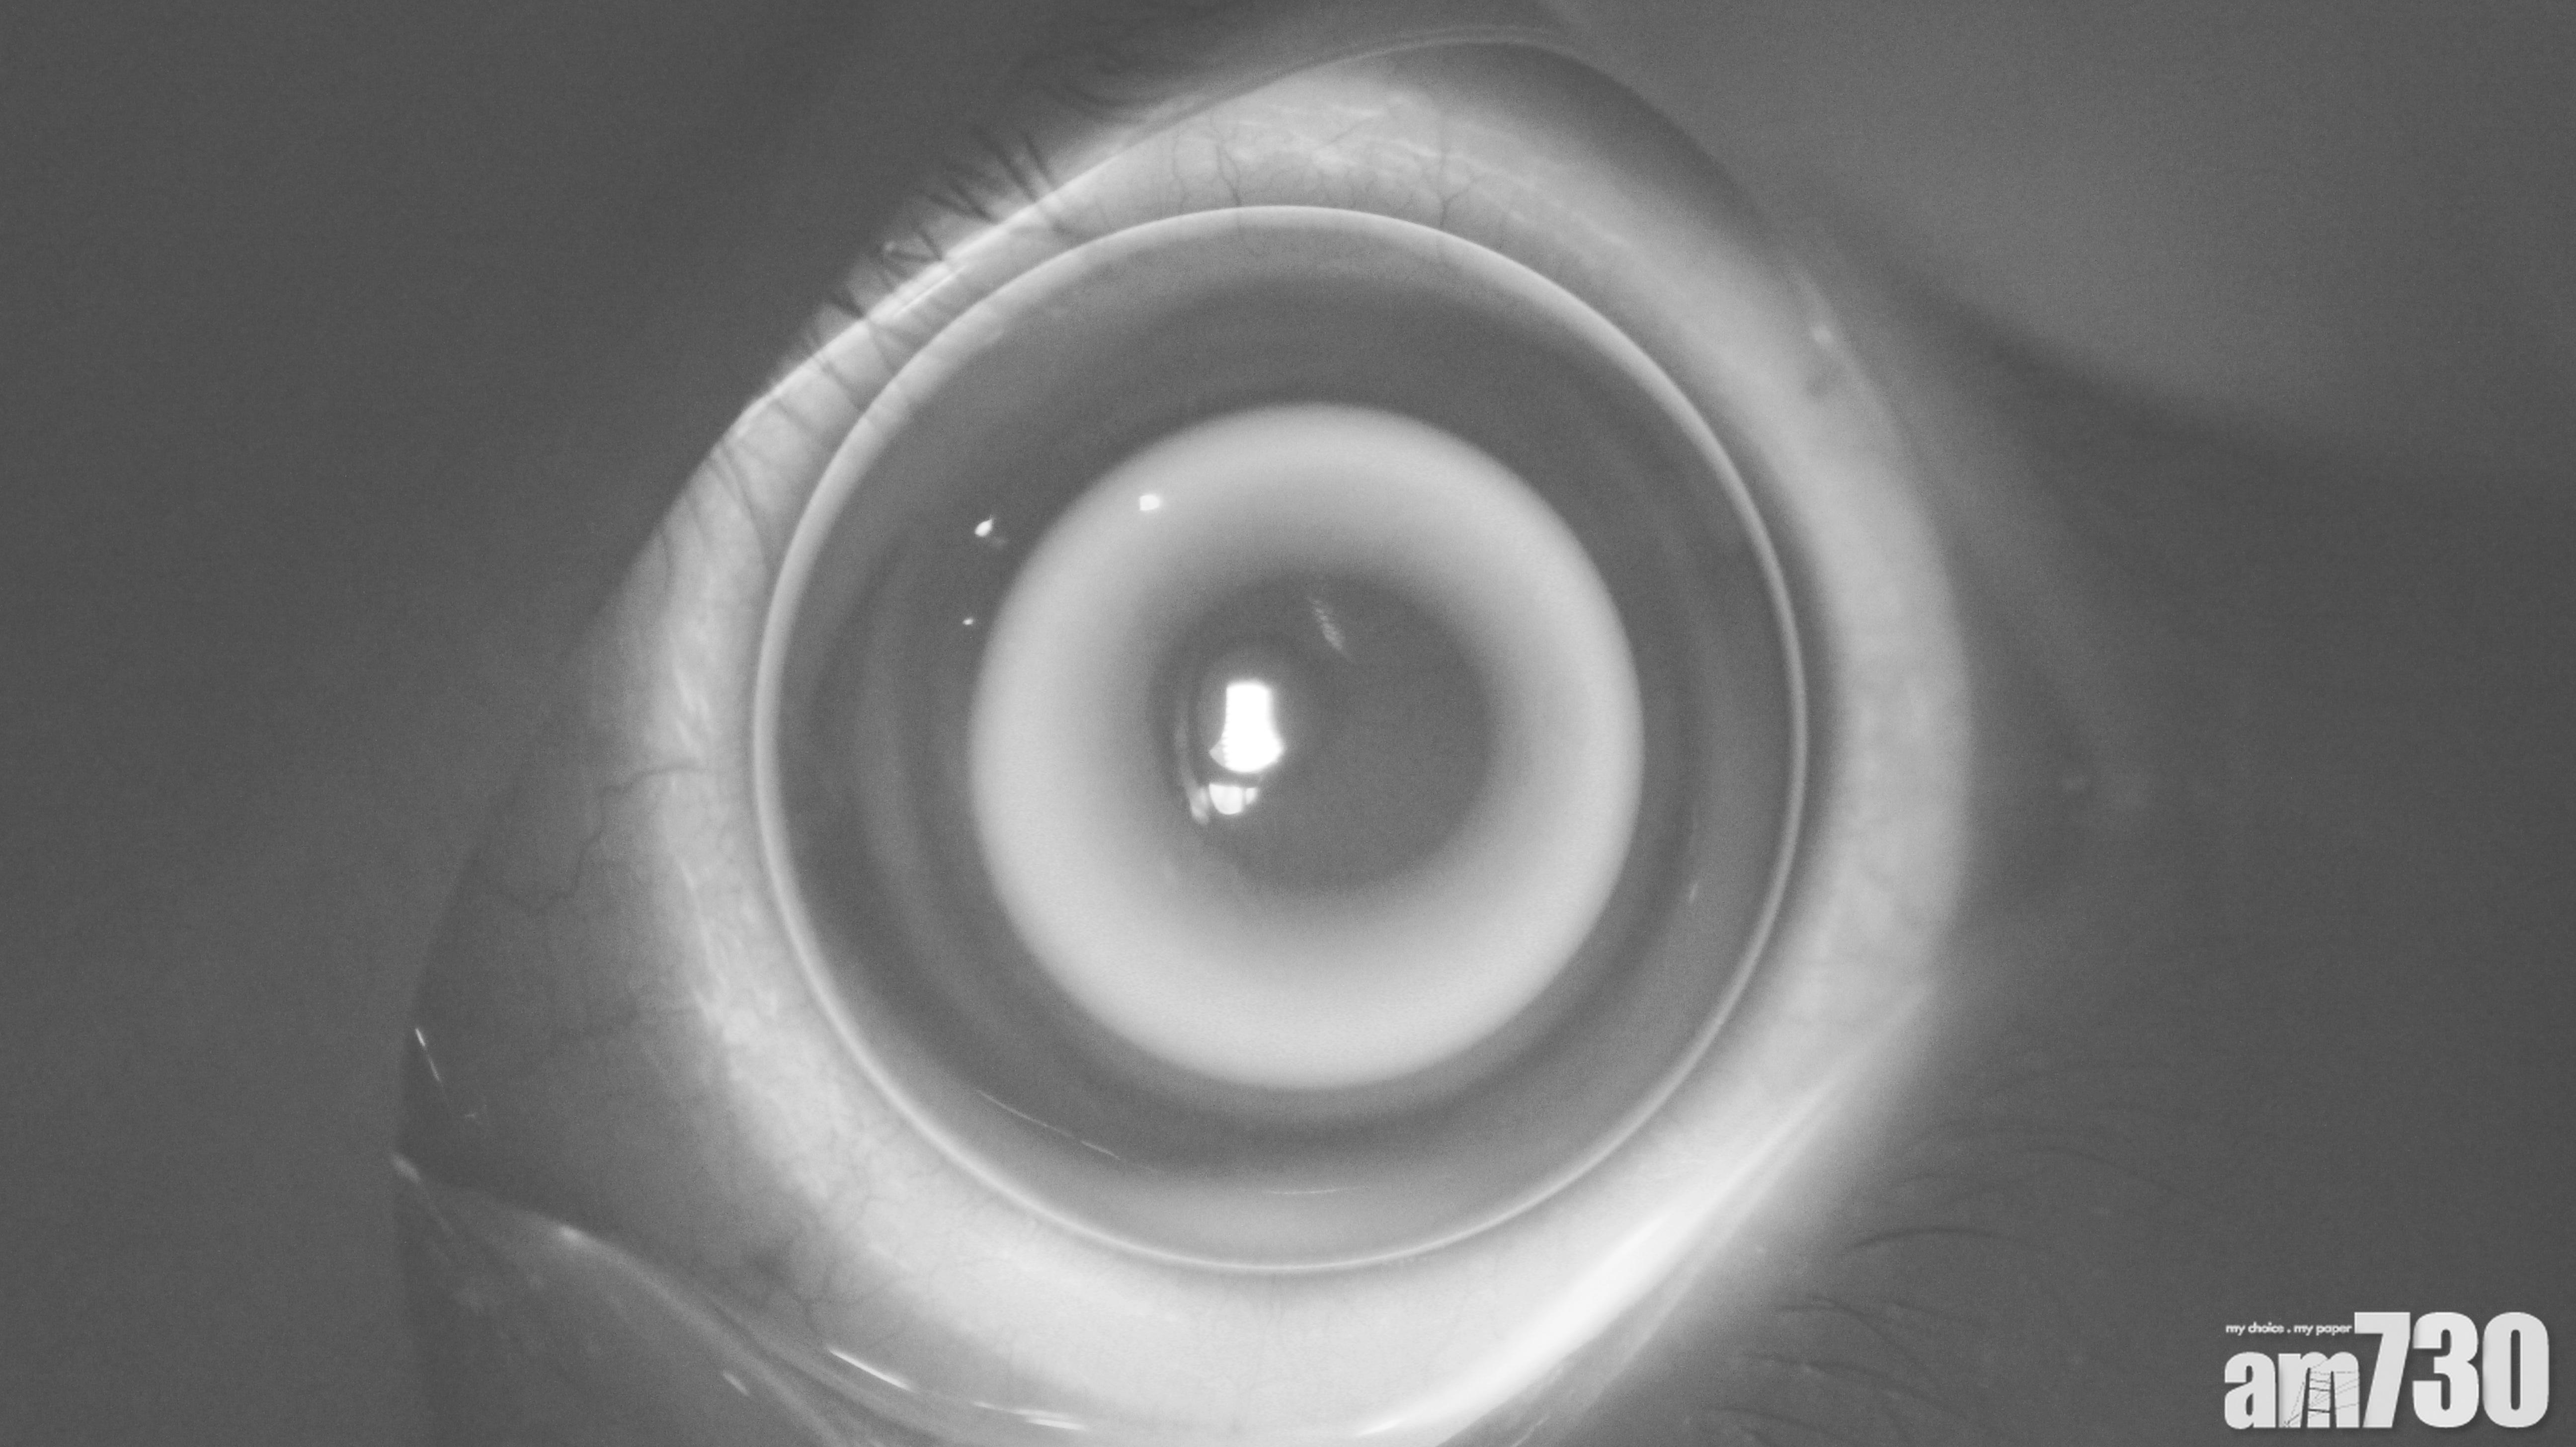

- OK鏡:即角膜塑形隱形眼鏡,若使用方法正確,可減慢近視加深。惟家長需特別注意其風險,由於需要晚上配戴, 加上除戴隱形眼鏡的過程會接觸眼睛,須注意衛生,否則可能會導致角膜感染,結痂,以致視力永久受損。另外,此治療不一定適用於所有的眼睛情況,家長使用前須諮詢眼科醫生的意見。

近年OK鏡十分受家長歡迎,但醫生建議須注意其風險。